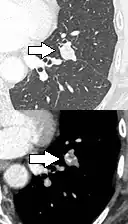

- Location: Upper lobe location is a risk factor for cancer, while a location close to a fissure or the pleura indicates a benign lymph node,[8] especially if having a triangular shape.[9]

- Margin morphology: a spiculated margin is a risk factor for cancer.[8] Benign causes tend to have a well defined border, whereas lobulated lesions or those with an irregular margin extending into the neighbouring tissue tend to be malignant.[10] In particular, spiculations are highly predictive of malignancy with a positive predictive value up to 90%.[9] Also, a "notch sign", which is an abrupt indentation of the nodule, increases the risk of cancer, but may also be found in granulomatous diseases.[9]

-

subpleural nodule.[9] -

Round well-delineated solid lung nodule with smooth border.[9] -

Lobulated nodule.[9] -

Spiculated lung nodule.[9] -

A "notch sign".[9] -

A triangular perifissural node can be diagnosed as a benign lymph node.[9]